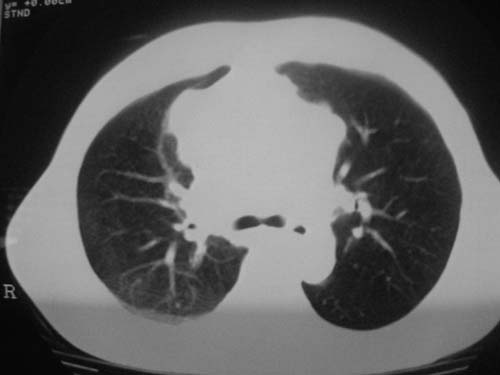

以下是引用科室第一人在2010-3-25 20:30:00的发言:[br]1:纵膈肿瘤性病变,恶性胸腺瘤可能性大伴纵膈右肺门淋巴结转移,右侧胸腔积液。[br]2:右侧肺门肿瘤性病变,纵膈淋巴结转移,右侧胸腔积液。右下叶转移。

以下是引用子期在2010-3-25 21:00:00的发言:[br]先考虑右中央型肺癌伴转移。

以下是引用江广1996在2010-3-25 22:49:00的发言:[br]通常肺癌向纵隔转移多见,纵隔肿瘤向肺内转移少见(有的表现为向肺内侵润)。本例以一元论考虑:右中心型肺癌并纵隔淋巴等多处转移。[br][br][本贴已被 江广1996 于 2010-3-25 22:50:07 修改过]

以下是引用yangyudong333在2010-3-26 6:43:00的发言:[br]“冰冻纵膈”,考虑纵膈淋巴瘤伴肺内及胸膜侵润。